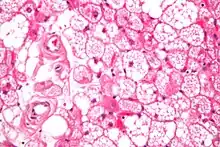

| Micrograph of a hibernoma. H&E stain. | |

The tumors histologically resemble brown fat. There are four histologic types recognized, but one is the most frequently seen (typical). There is a background of rich vascularity.

- Lobular type: Variable degrees of differentiation of uniform, round to oval cells with granular eosinophilic cells with prominent borders, alternating with coarsely multivacuolated fat cells (pale cells). There are usually small centrally placed nuclei without pleomorphism. The cells have large cytoplasmic lipid droplets interspersed throughout.[3][4]

- Myxoid variant: Loose, basophilic matrix, with thick fibrous septa, and foamy histiocytes

- Lipoma-like variant: Univacuolated lipocytes, with only isolated hibernoma cells

- Spindle cell variant: Spindle cell lipoma combined with hibernoma